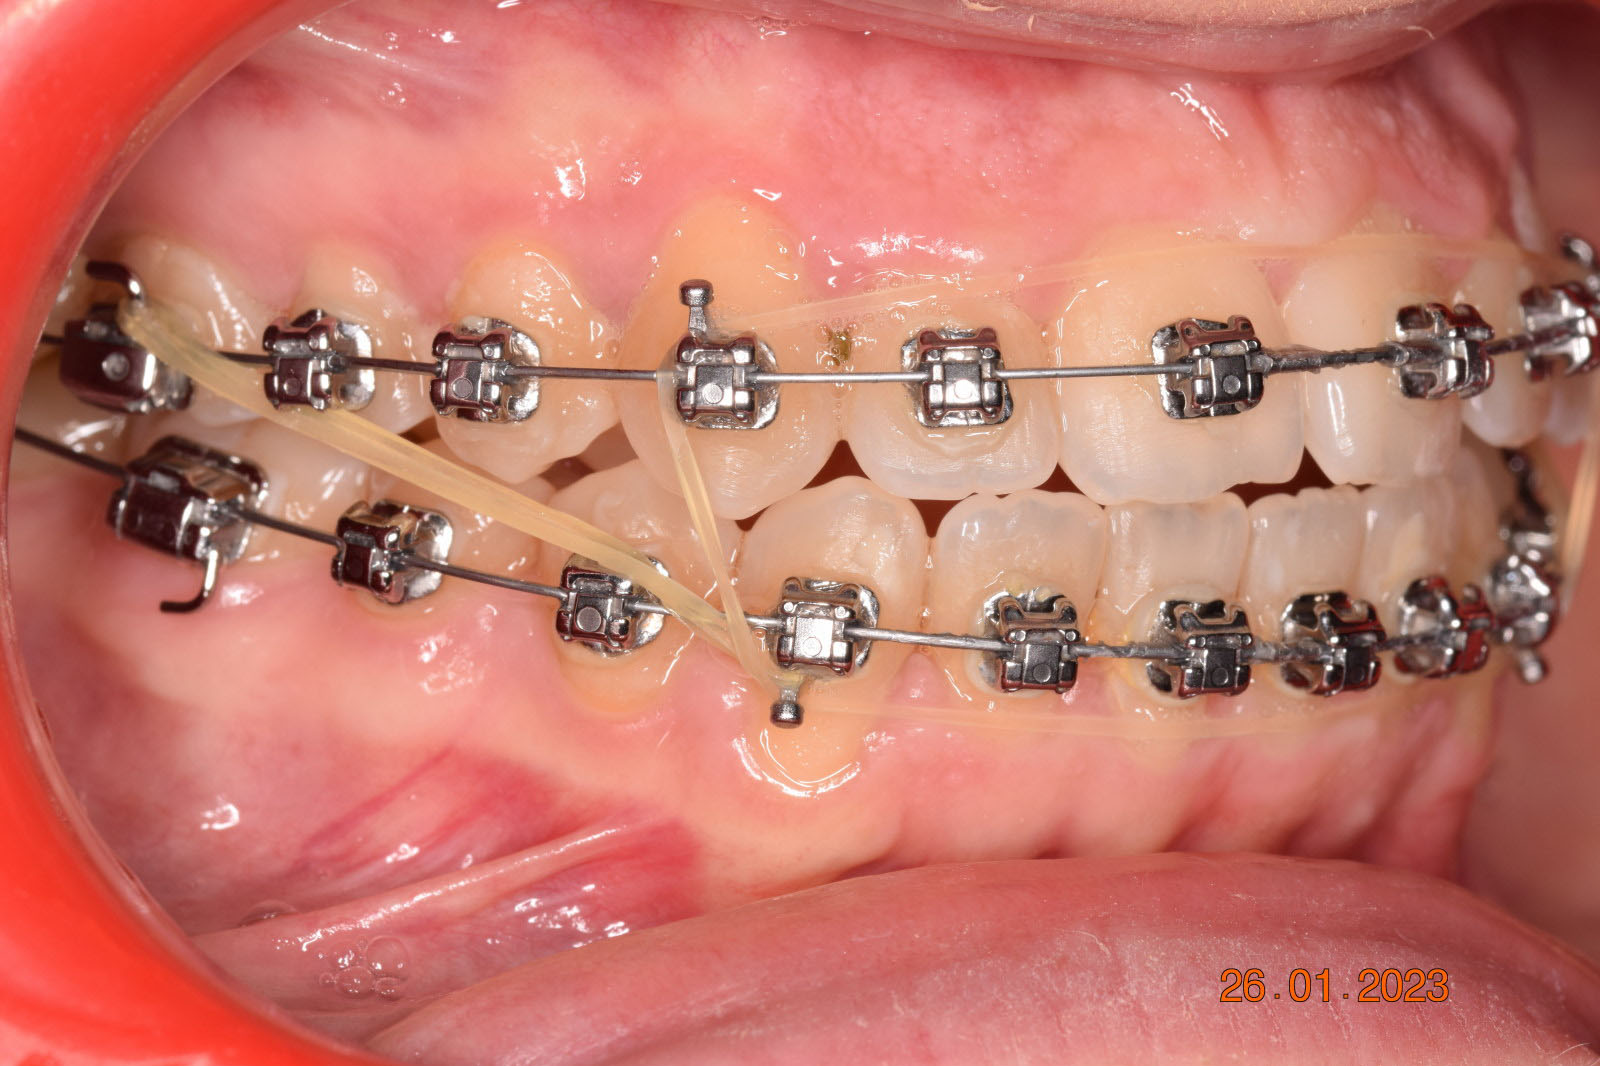

The treatment began in 2017. Given the patient’s preference for less visible brackets, Damon Clear brackets were selected. High torque upper cuspids and low torque upper incisors were chosen to offer the best torque control for upper arch development. For the lower arch, there were no alternative bracket configurations available. Bite turbos were applied to the upper second molars.

The results were unsatisfactory and the patient began losing interest in the treatment. Dr. Coca and the patient agreed to extend the treatment for six more months and then stop, regardless of the outcome.